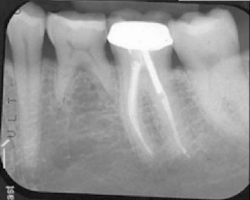

The patient was seen four months later for Stage II uncovering of her implant using a tissue punch and was sent to her restorative dentist for final impressions two weeks after that. Three months after the initial surgery, the patient returned with her final restoration in place for a soft-tissue exam and radiograph. Six months after surgery, she returned for a postdelivery radiograph, shown here. (I see every implant patient three months after seating the final restoration to check for residual cement, ensure that the restorative apparatus is fully seated, and check the soft- and hard-tissue response to the new restoration. This is an extremely important—and often overlooked visit—where problems are often noted that can cause significant damage to the bone and gingiva if early intervention is not initiated.) The bone levels were well-maintained around the implant platform, and the soft-tissue health was excellent. The patient reported a high degree of satisfaction with her new implant restoration.